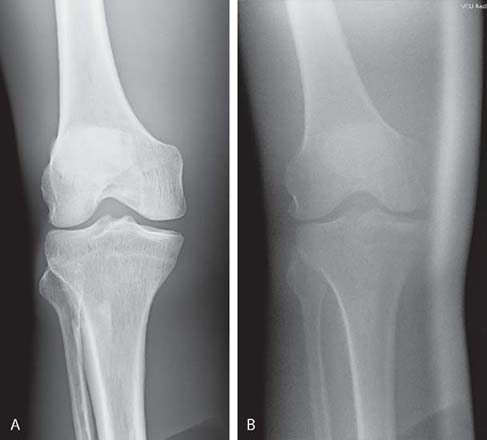

Grid alignment errors may be difficult to identify because the computer will adjust for exposure errors to the IR. However, adjusting the brightness during computer processing may not overcome a grid alignment error and still produce a poor-quality image (Fig. 7-25). When using a grid, the radiographer should pay close attention to the alignment of the grid to the x-ray tube and IR.

FIG. 7-25 Grid cutoff. A, Image created with proper alignment of computed radiography and no grid cutoff. B, Image created with off-level grid cutoff. The overall brightness was maintained, but the image quality is poor. (From Johnston JN, Fauber TL: Essentials of Radiographic Physics and Imaging, ed 3, St. Louis, 2020, Elsevier.)